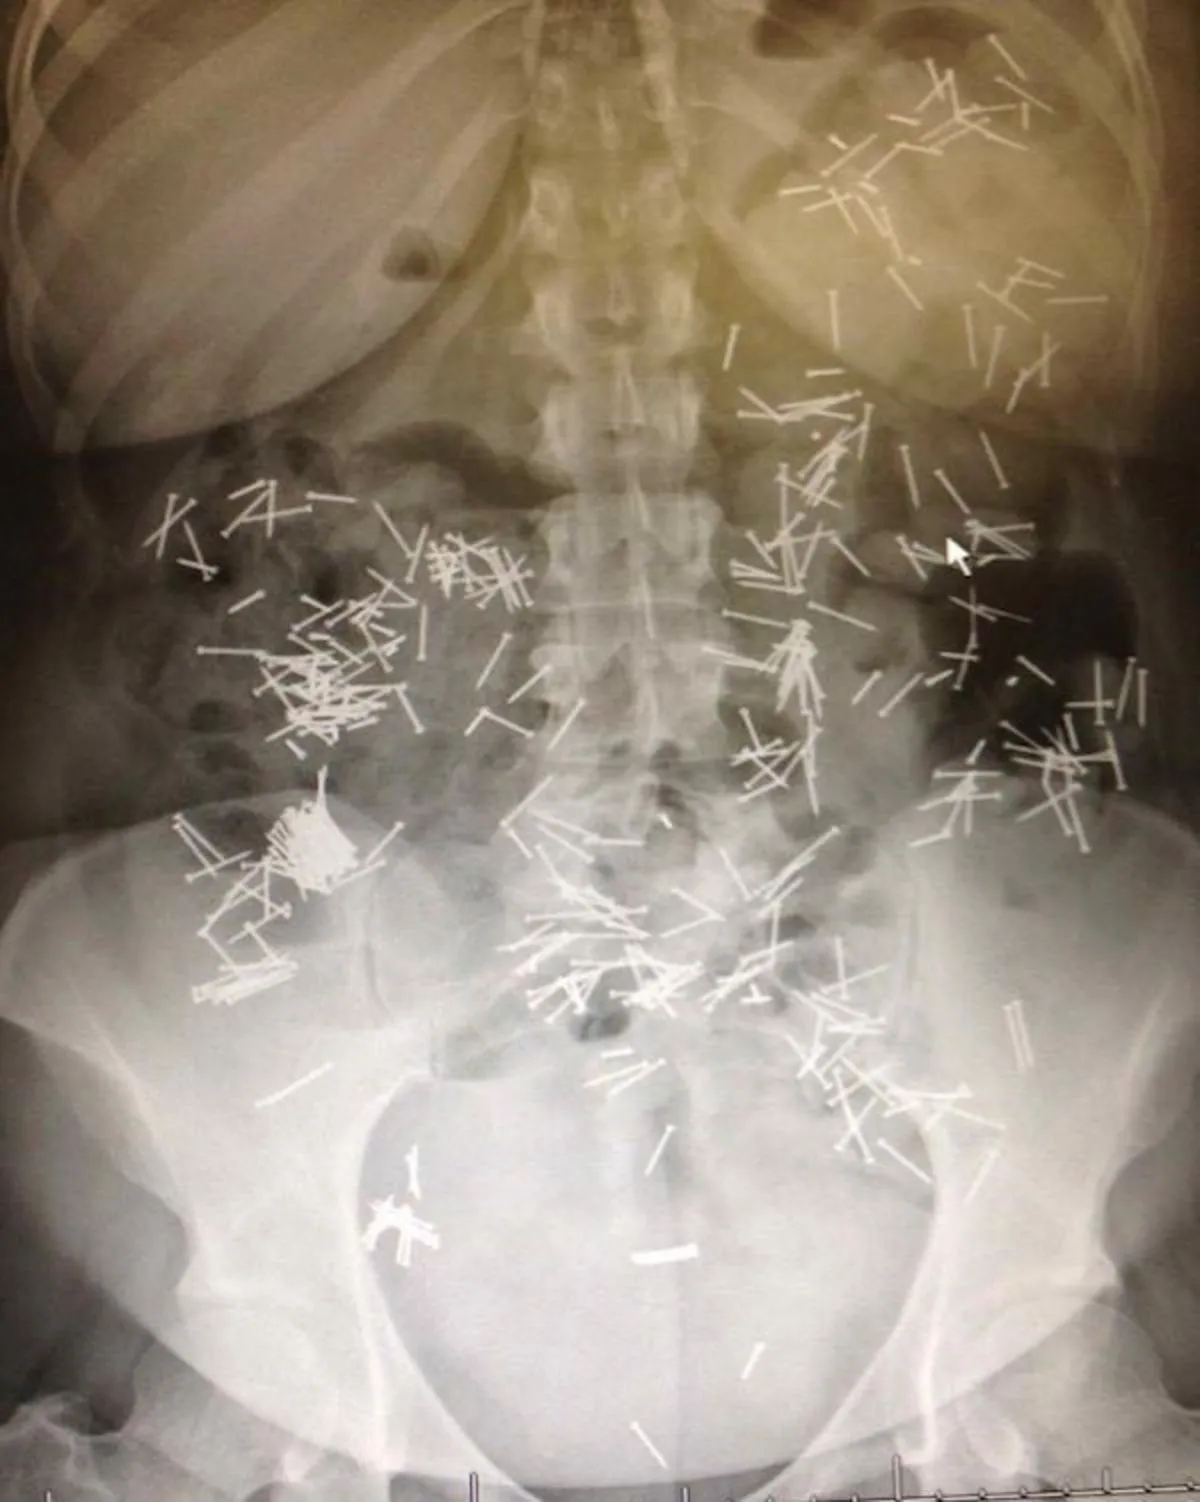

Он наглотался гвоздей, но избавился от них... естественным образом

Фото funnyjunk